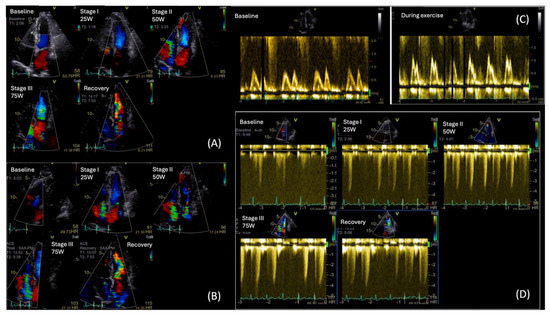

5. Stress Echocardiography

Unlike resting echocardiography, SE reveals impairment in systolic and diastolic function, providing an assay of increased LVFP—key pathophysiologic features of DBCM [87]. Following the subclinical changes, a reduced myocardial reserve—the heart’s capacity to increase function in response to stress- usually occurs long before the development of overt cardiac dysfunction at rest [88]. As the disease progresses, the heart develops impaired relaxation and increased stiffness, resulting in diastolic dysfunction. This is often the first detectable abnormality in dynamic testing [89].

5.1. Exercise Stress Echocardiography

Exercise stress echocardiography (ESE) is a valuable tool for unmasking diastolic dysfunction in patients with unexplained dyspnea and/or fatigue, particularly when the diagnosis remains uncertain due to inconclusive resting echocardiographic findings. The 2020 HFA–PEFF diagnostic algorithm recommends the use of ESE to confirm the diagnosis of HFpEF in cases of intermediate HFA-PEFF score [4,5,86]. The latter score is initially calculated from resting echocardiography parameters and natriuretic peptides levels. The addition of ESE is to reveal exaggerated elevations in LVFP and pulmonary artery systolic pressure (PASP) on exertion.

In clinical practice, ESE is commonly performed using a semi-supine ergocycle protocol with incrementally increasing workload (typically 25-watt increments every 2 min), enabling optimal image acquisition during each exercise stage [88,89,90]. Alternatively, upright bicycle and treadmill protocols are also used, particularly in centers without access to supine ergometry. However, these may limit real-time image acquisition, which can introduce variability due to rapid heart rate recovery [91].

During exercise, a rise in E/E′ and an increase in TR peak velocity (TRVpeak) are often observed in patients with HFpEF, reflecting an abnormal surge in LVFP and PASP, respectively. As heart rate rises, the impaired relaxation in diabetes leads to a disproportionate rise in LVFP and pulmonary pressures, exposing diastolic abnormalities not evident at rest [91,92,93]. Notably, according to the ESC consensus criteria, an exercise E/e′ ≥ 15 and/or TRVpeak > 3.4 m/s are indicative of HFpEF during stress [90]. Moreover, ESE may show an inadequate increase in stroke volume despite rising LVFP, differentiating cardiac limitations from non-cardiac causes of exercise intolerance (Figure 6).

While standard diastolic ESE remains the cornerstone in the evaluation of unexplained dyspnea in patients with suspected HFpEF, recent evidence suggests that a significant subset of symptomatic patients with negative ESE findings may still have HFpEF and a cardiopulmonary exercise test (CPET) could be useful. In a study by Verwerft et al., the use of exercise-induced pulmonary HTN, defined by an elevated mean pulmonary artery pressure to cardiac output slope (mPAP/CO slope > 3 mmHg/L/min), was shown to unmask abnormal cardiopulmonary reserve and impaired pulmonary vascular adaptation in patients with unexplained exertional dyspnea but normal ESE diastolic parameters [94]. Among these patients, elevated mPAP/CO slope strongly correlated with reduced peak VO2 and reduced ventilatory efficiency, supporting its diagnostic and prognostic utility in identifying HFpEF beyond classical criteria [94].

This approach is especially relevant in patients where DBCM may remain undetected by standard evaluation at its early stages. In the study by Gojevic et al., a higher percentage of diabetic patients with exertional dyspnea showed elevated mPAP/CO slopes during exercise compared to asymptomatic diabetic controls; however, the difference between groups was not statistically significant. This underscores the complexity of interpretation and highlights the need for further research to define the diagnostic and prognostic role of mPAP/CO slope in diabetic cardiomyopathy [95]. From the practical point of view, the combination of echocardiography and CPET has the potential for higher accuracy than ESE per se.

Beyond diastolic assessment, ESE evaluates contractile reserve, often impaired in the early stages of DBCM, even when the resting LVEF > 50%. A failure of exercise to increase LVEF or stroke volume may be an early sign of HFpEF [96]. In the diabetic population, GLS is often mildly reduced at rest and fails to augment appropriately during stress, indicating impaired systolic reserve [97]. Likewise, a blunted rise in peak systolic strain rate (SRs) during ESE reflects reduced contractile reserve, making these strain-based measures valuable for early diagnosis of subclinical DBCM [97].

MW provides an assessment of LV function and GLS by incorporating afterload assessment via the blood pressure measurement [98]. While MW has proven effective in identifying early, subtle abnormalities in HFpEF patients at rest, only a limited number of studies have investigated how these parameters respond to physiological stress. A dynamic evaluation may reveal impairment in these indices during stress that is masked at rest [98,99]. In the study of Zhang et al. (2025), which enrolled 40 patients with HFpEF and 40 normotensive controls, the HFpEF group demonstrated significantly lower increases in GWI and GCW, along with significantly greater increases in GWW and a more pronounced decline in GWE from rest to peak exercise compared to controls; these changes in MWI were closely associated with reduced exercise tolerance [100]. Inherent drawbacks of STE analysis in higher heart rates with reduced frame rates limit their clinical applicability [101].